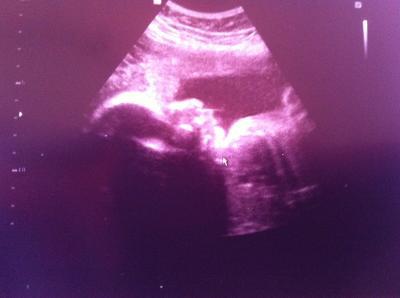

Und hier ein Screenshot von dem 3D ultraschall, als sie uns Anlächelte

Bild zu